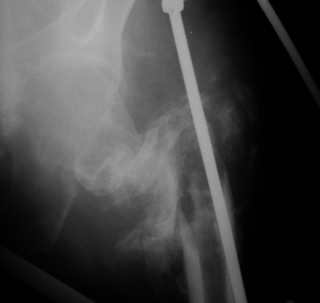

Вот снимки по свежей ситуации, парень 19 лет, длинный оскольчатый перелом бедра от шейки до в-с/3. давно уже ходит на своих ногах.

Представленные Вами рентгенограммы действительно являются примером качественной фиксации спице-стержневым аппаратом. Они, как ни что другое, многое иллюстрируют.

Кроме того, было бы ошибкой ставить знак равенства между нашим и Вашим пациентами. Они не только не похожи, разница между ними просто огромная. Говорю это не для того, чтобы задеть Вас или обидеть. Ни в коем случае. Просто теперь я понимаю, что Ваше мнением строится на простом преломлении Ваших подходов к лечению пациентов со свежими переломами, на ситуацию, абсолютно несопоставимую, подобную нашей.